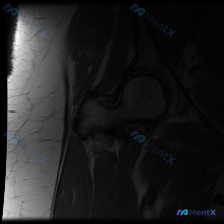

最近看到一份肩部MRI-T1轴位影像的分析报告,内容如下: 影像分析要点: - 单张T1轴位片显示肱骨、关节盂形态正常,肩胛下肌腱完整 - 前后盂唇形态尚可,未见明显撕裂、断裂或剥离征象 - 无明显骨折、脱位或严重退变证据 - 报告指出,单张T1轴位片不能全面评估肩关节病理,尤其是盂唇细微病变(如S...

整理了一个病例讨论材料,患者临床怀疑盂唇病变,目前只提供了一张髋关节MRI T1矢状位图像。从这张图看,股骨头形态规整、髋臼结构正常、关节间隙清晰,盂唇也显示完整,但总觉得单一序列评估盂唇有局限性。大家怎么看这个病例?下一步该重点做哪些评估?